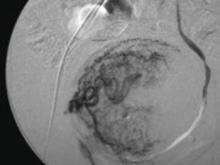

In UAE, a trained interventional radiologist performs percutaneous cannulation of the femoral artery. Embolization of the uterine artery and its branches (FIGURE 1) is accomplished with gelatin sponges, polyvinyl alcohol particles (PVA), or tris-acryl gelatin microspheres under fluoroscopic guidance. Total radiation exposure is equivalent to one to two computed tomography (CT) scans.

FIGURE 1 Target: blood supply

Arteriogram showing blood supply to fibroid to be targeted during uterine artery embolization.